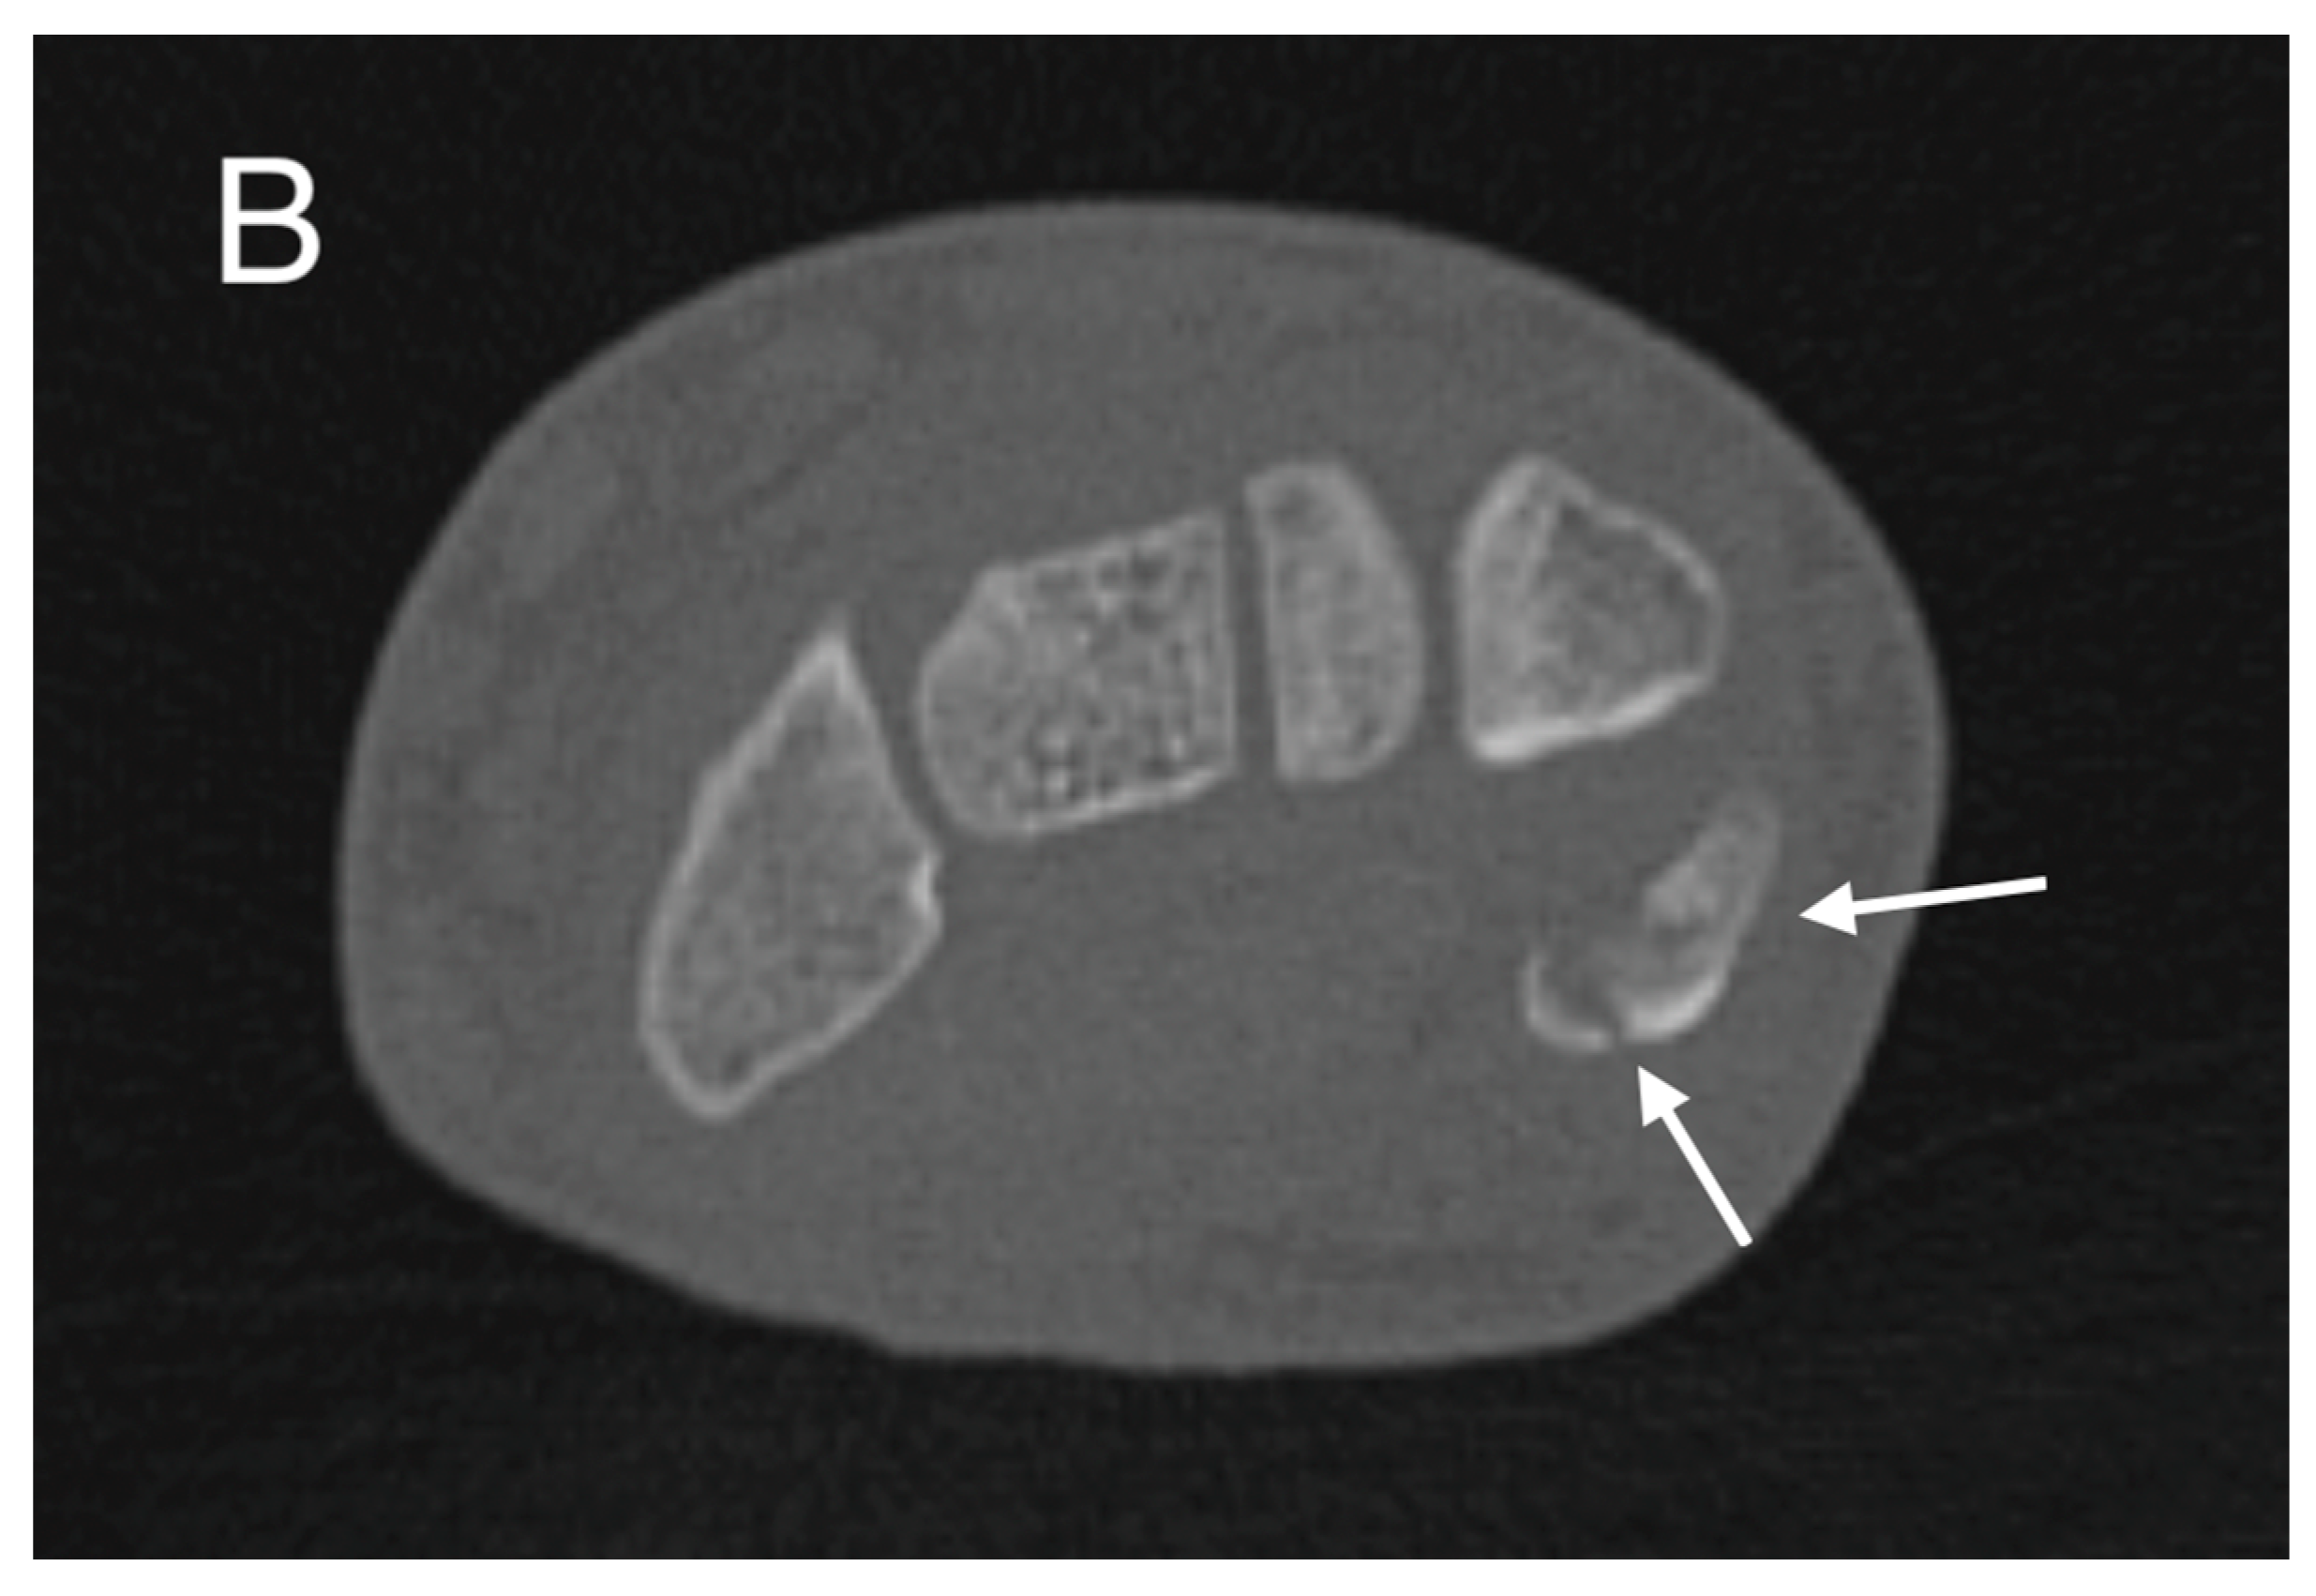

Figure 2.

Initial CT study with sagittal (A) and axial (B) images showing a non-displaced fracture of the pisiform bone (white arrows).